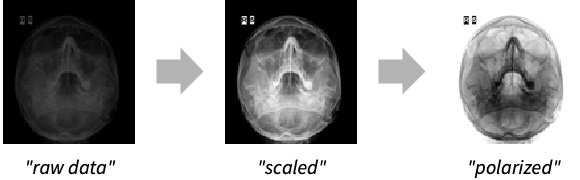

"Modality" Automatic modality transform to make data manufacturer independent "Polarity" Automatic whether to assume minimum value as black or white "Presentation" Automatic whether to transform to human perceptual response "ScalingWindow" Automatic scaling method to use for importing data, also known as values of interest (VOI) - By default, the modality transformation specified in the file is used. Use "Modality"None to disable this transform.

Import the image with default data transformations applied:

Import the image without transformations:

Import the image with specific scaling values and reversed polarity:

Compare how disabling modality transformation and changing polarity affects the imported image: